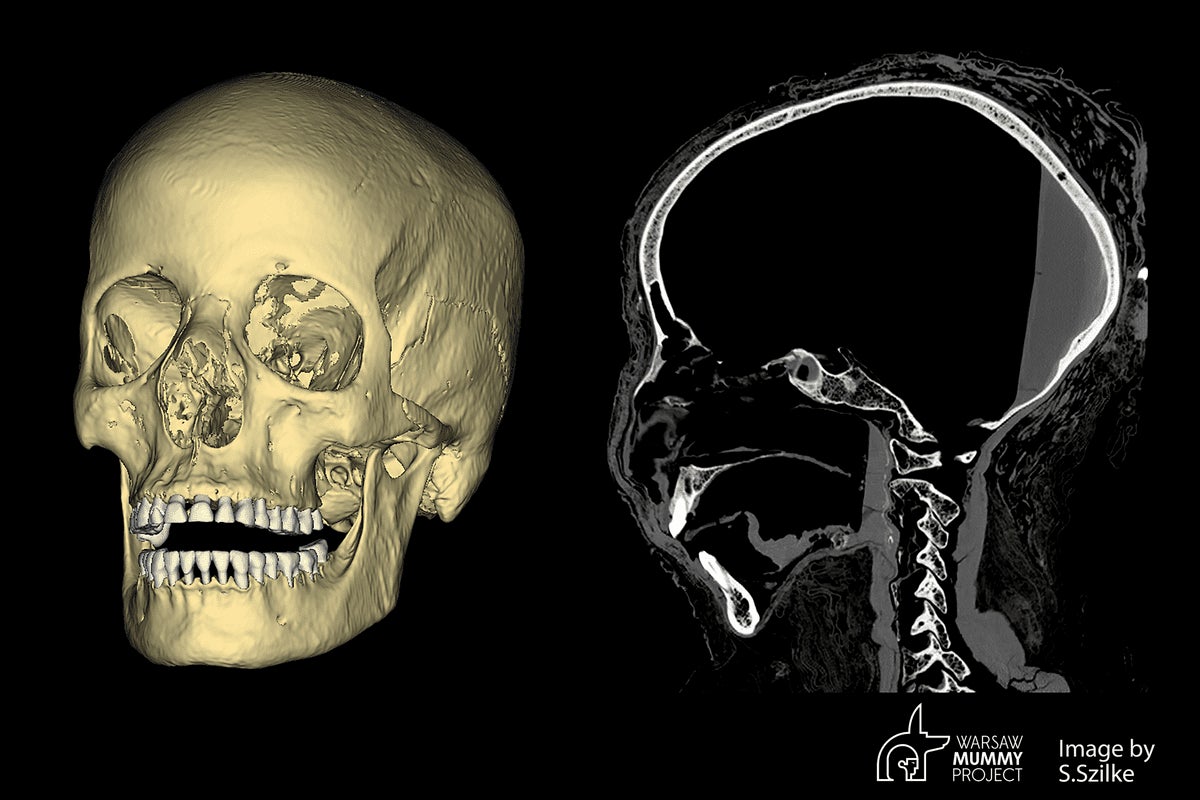

En las tomografías computarizadas se puede ver un pequeño cambio patológico, de unos 7 milímetros de diámetro, una lesión redonda que rodea un espacio vacío, en el hueso detrás de la órbita izquierda. Lo más probable es que se trate de un cambio causado por un tumor, posiblemente un sitio metastásico. Este tipo de cambios metastásicos en los huesos del cráneo se dan, entre otros, después de un adenoma, pero si fuera este tipo de tumor, las pruebas histopatológicas nos darían una respuesta definitiva. Además, hay grandes cavidades en los huesos de la cara, incluida la cavidad nasal, los senos maxilares y la parte palatina de los huesos maxilares. Los cambios en los huesos craneofaciales se corresponden con el cáncer nasofaríngeo en pacientes modernos.